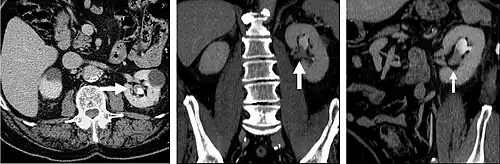

CT urography (CTU) is commonly used in the evaluation of hematuria, and specifically tailored to image the renal collecting system, ureters and bladder in addition to the renal parenchyma.

The CT scan will image the urinary tract, including the kidney, ureters, bladder, and urethra.[3] It does this by taking many cross-sectional images that can be computationally arranged so as to provide 3D information.[3] The scan itself usually involves a CT scan without contrast (a non-contrast phase), a CT scan while the contrast is within the kidneys (a parenchymal phase), and a CT scan taken while the contrast travels through the renal tract (an excretory phase).[4]